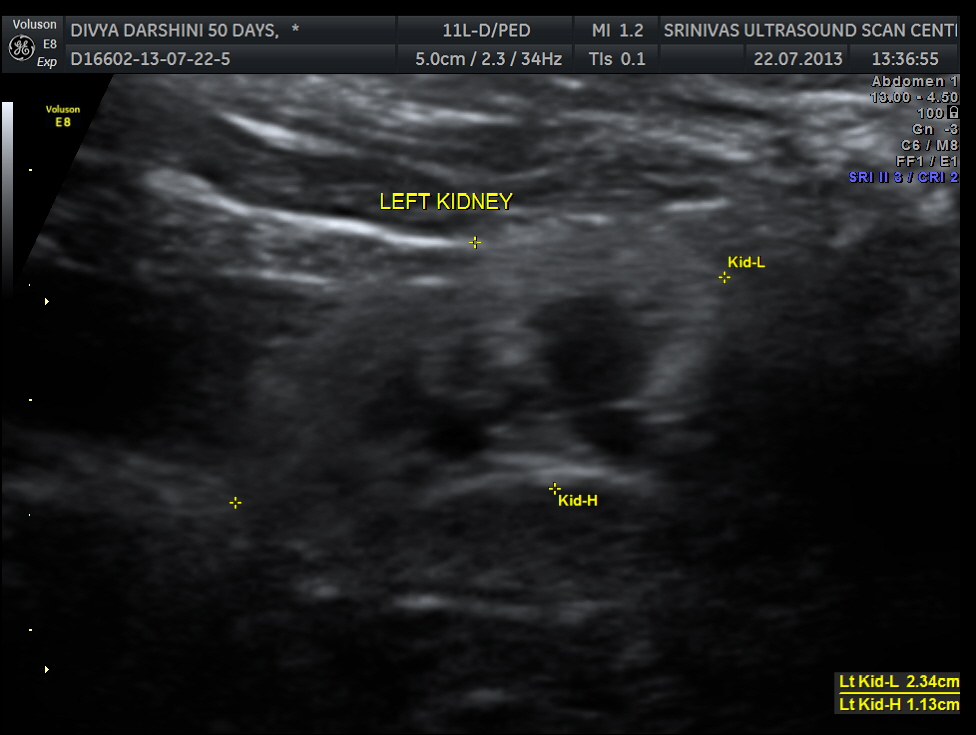

The following two pictures show the hyperechoic kidneys of the child with mild pelvi calyceal dilatation . The kidneys were picked up only with the 11 mhz transducer.

The IVS straddling the aorta is prominently seen ; The RV is mildly dilated . Though the pulmonary artery was difficult to comment on , I would still go with TETRALOGY OF FALLOT with RENAL DYSPLASIA , which makes it complicated.